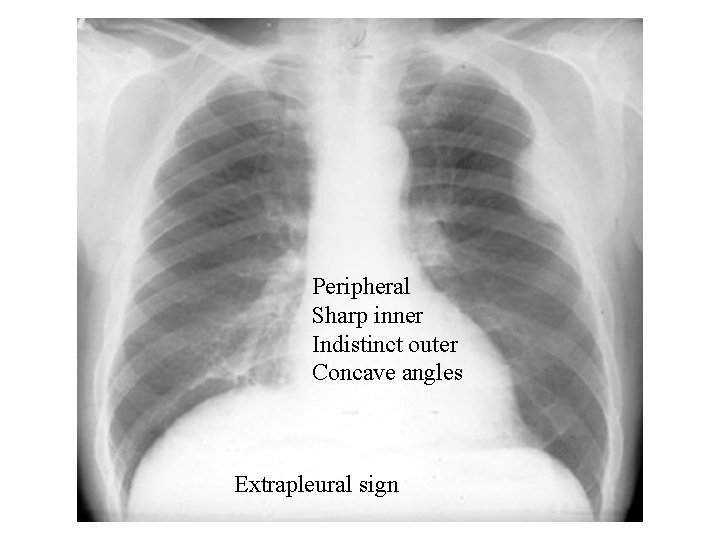

Extrapleural sign

Peripheral Sharp inner Indistinct outer Concave angles Extrapleural sign